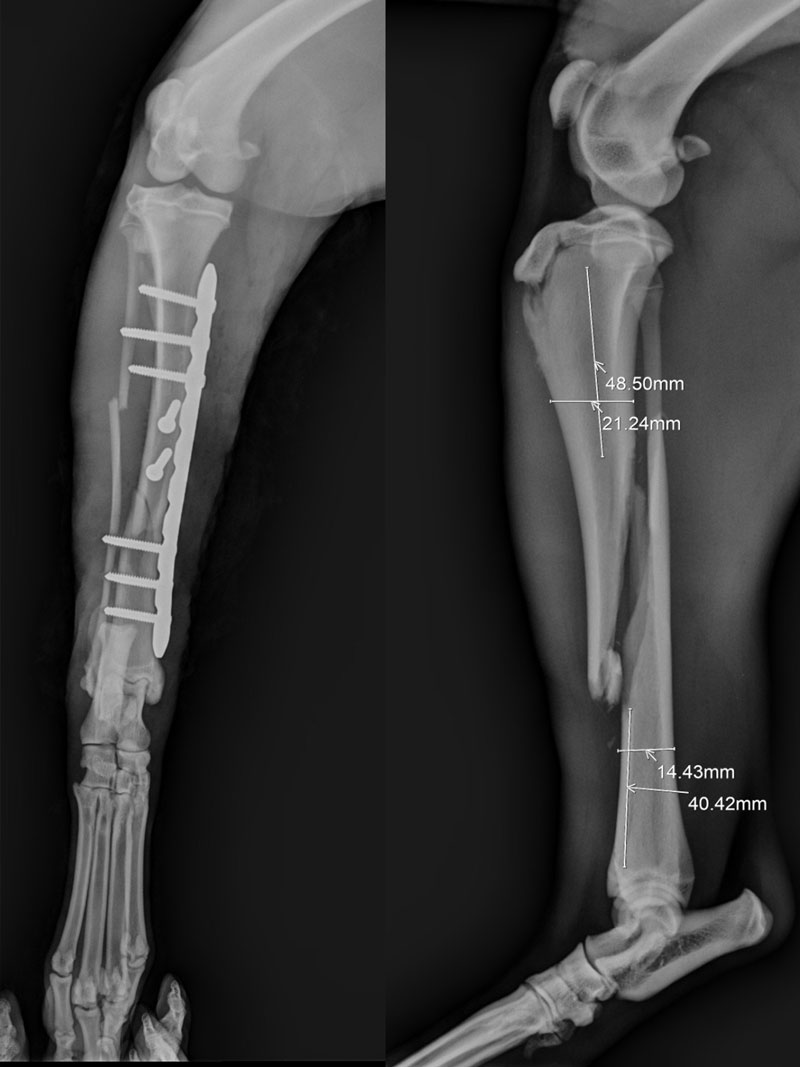

Servicio integral de traumatología: tecnología específica, amplio stock de insumos y una respuesta rápida y eficaz a lesiones óseas, musculares y articulares.

Cirugía especializada con anestesia inhalatoria: realizamos procedimientos seguros y avanzados, con una alta tasa de resolución y recuperación.Con más de 30 años de experiencia, nos respalda una trayectoria basada en la excelencia, el compromiso y la constante actualización profesional. Tu mascota está en las mejores manos.